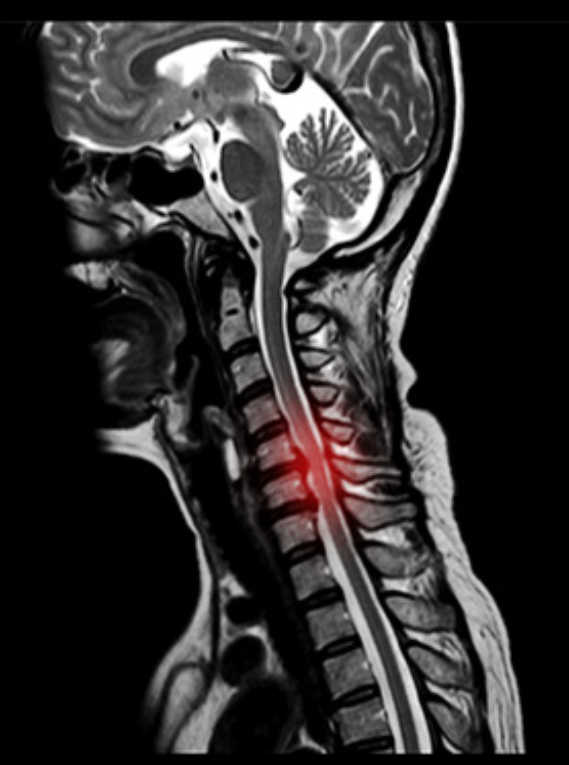

首の椎間板というクッションが破れて,中身(髄核)が後ろの神経を押して症状を引き起こしている状態を頸椎椎間板ヘルニアと言います。

発症年齢は30〜50歳代に多く、症状としては首の痛み、肩甲骨の痛みしびれ、肩や腕、手の痛みしびれを生じることが多いです(1)。

首のMRIで神経の圧迫所見がある場合確定診断します。

また頸椎MRIで脊髄の圧迫と信号変化があると頚髄症を強く考えます。